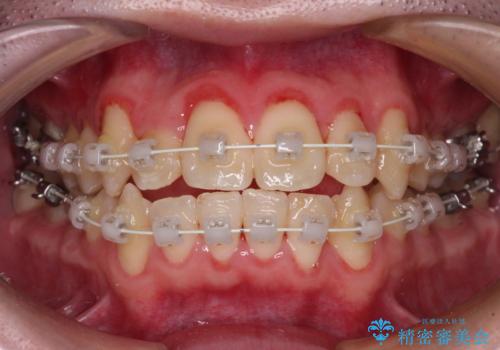

- 審美装置

- 治療期間

- 2年1ヶ月

シザーズバイトは強く咬合する奥歯を移動させるため、多くの場合においてワイヤー矯正の装置のみでは改善が困難となります。

奥歯の咬み合わせ改善は治療初期からしっかりとアプローチする必要があるため、補助装置を積極的に利用します。